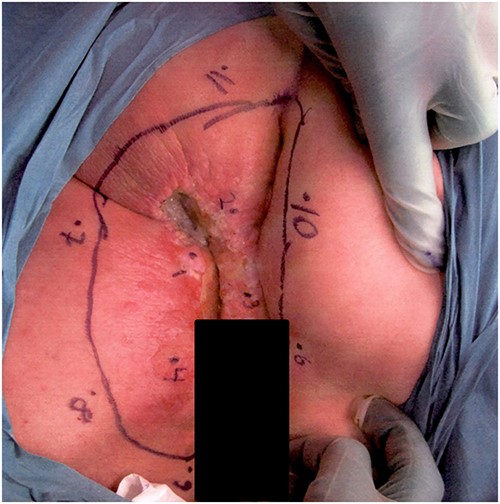

An 83-year-old man with a history of hypertension and asthma but no previous abdominal surgery was referred to the Department of General Surgery with an 8 × 8 cm perianal necrosis at the scrotal base (Fig. 1). Nineteen years earlier, the patient had been diagnosed with PPD without invasiveness located in the same area and treated with RT twice over 4 years with a total radiation dose of 82 Gy. The patient was examined by colorectal surgeons, plastic surgeons, and urologists. The lesion was located at the scrotal base, with a necrotic ulcer in the perianal area. Initially, the condition was interpreted as a side effect of RT, but, after multiple biopsies, histopathological examination showed Paget without signs of invasiveness.

Photograph of the affected lesion in our first patient. Mapping biopsies confirms Paget’s disease in macroscopically normal tissue.

Clinical workup including normal colonoscopy and MRI of the lower abdomen excluded involvement of the urethra or corpora cavernosum. FDG-PET-CT demonstrated hypermetabolism in the perianal area and in both groins, but no findings indicated malignancy elsewhere. The multidisciplinary conference recommended an abdominoperineal rectal excision, including a muscle flap for perineal closure. Before surgery, multiple mapping biopsies of surrounding macroscopically normal tissue also showed Paget’s disease.